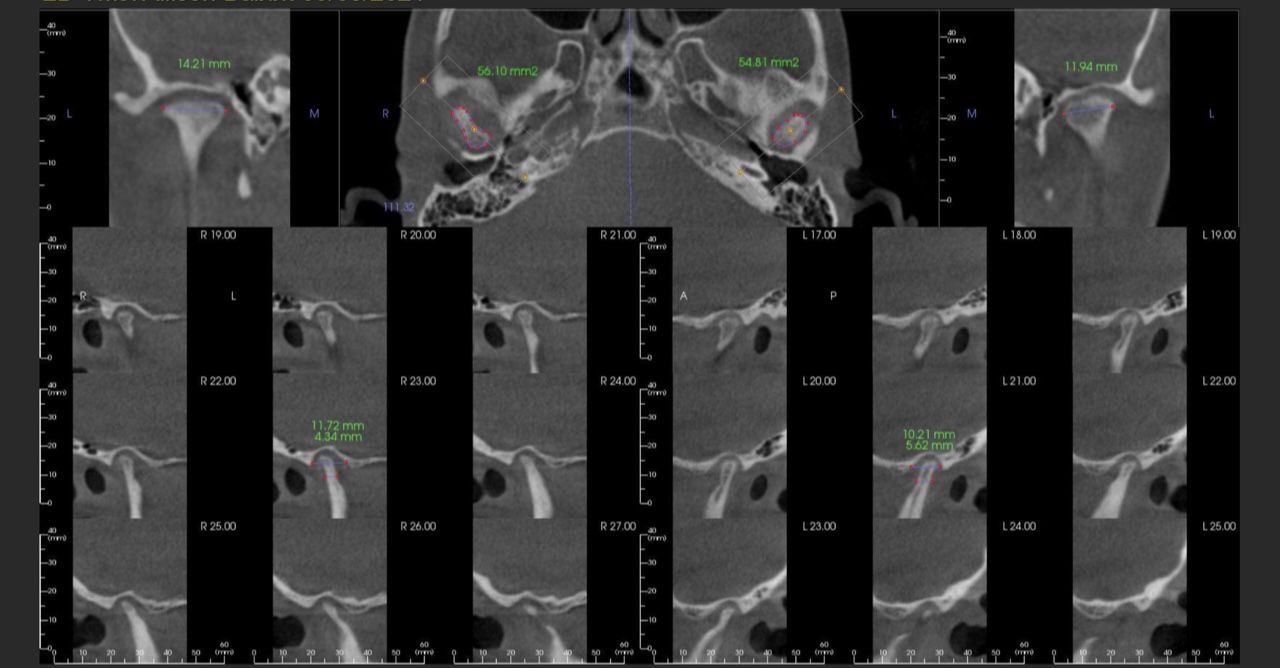

- The importance of imaging and its role in your specific diagnosis and risk assessment

- How to take, order and interpret both CT/MRI images